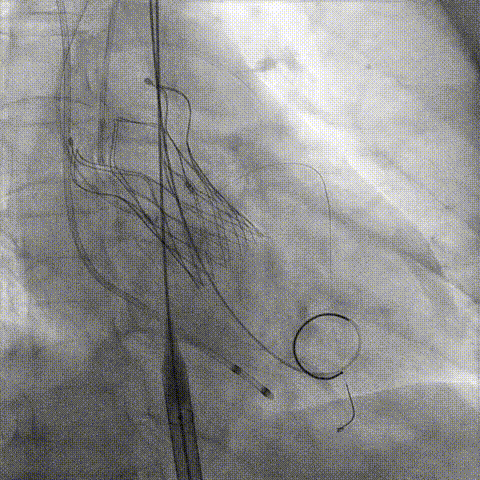

冠脉造影

手术策略和器械选择

预置Telescope™导引延长导管及导丝保护左冠,

18mm球囊预扩张再次评估冠脉闭塞风险。

Telescope™+Runthrough

18mm*40mm 预扩张

预埋 Resolute Integrity 3.5*26mm

再次评估左冠开口

第一次释放

再次评估左冠开口,考虑调整瓣膜深度

回收后调整深度,再次释放

评估左冠开口

左冠开口切线位造影

决定左冠烟囱支架保护冠脉

调整支架位置

释放冠脉支架

释放瓣膜

造影评估

支架内后扩张

根部造影